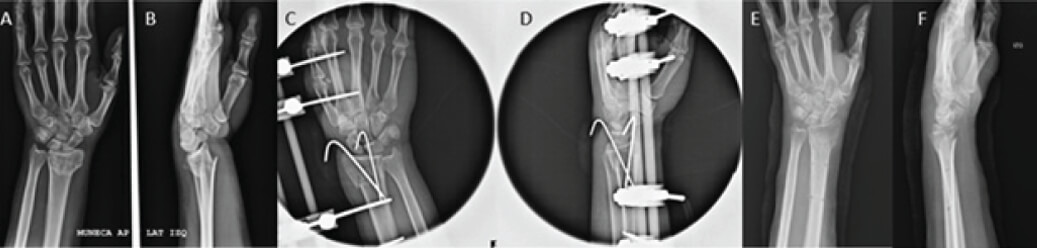

Los pacientes fueron intervenidos quirúrgicamente bajo anestesia general o regional endovenosa, en mesa de mano radio lúcida y bajo visión fluoroscópica, para el grupo de fijadores externos, se realizó una reducción cerrada, fijación percutánea de los fragmentos óseos con 2 o 3 alambres de Kirschner de 1,5 mm de diámetro cruzados, luego una neutralización sin distracción con un fijador externo doble barra tipo Baummer® con 2 pines de 2,0 mm en el segundo metacarpiano, pasados con la metacarpo falángica en 90°, y dos pines de 2,7 mm en el radio proximal al foco de fractura (figura 1A, 1B, 1B, 1C, 1D, 1E, 1F), cura de los pines y alambre con gasa y Coban®. El grupo tratado con placas volares se realizó a través del abordaje volar de Henry en la muñeca y antebrazo distal, con reducción abierta y osteosíntesis con PVEA (figura 2A, 2B, 2C, 2D), e inmovilización con férula antebraquio palmar. En ambos grupos se realizó corrección de la altura e inclinación radial, y una inclinación volar de 0° a 15°, egresando con la indicación de iniciar con los ejercicios para los dedos según formato del “five pack” (figura 3) desde el segundo día de postoperatorio.

Figura 1. 1A, 1B, 1B, 1C, 1D, 1E, 1F. Caso clínico tratado con AKFE

Figura 1. 1A, 1B, 1B, 1C, 1D, 1E, 1F.

Caso clínico tratado con AKFE